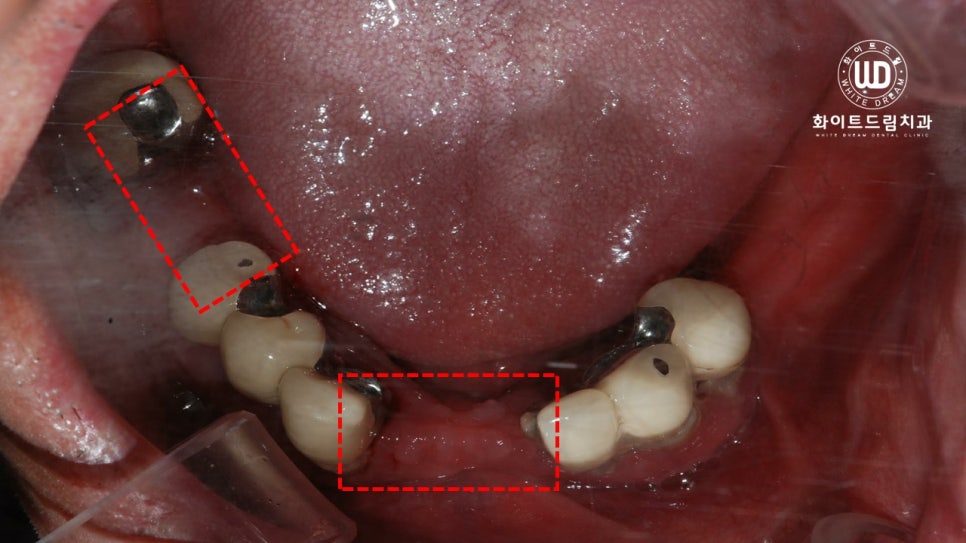

이번에 저희 치과에 내원해주신 환자분께서는 기존에 진료를 받아 부분틀니를 사용하고 계셨으며. 남아있는 치아 마저 전부 흔들려 불편함이 지속된다고 말씀해주셨는데요. 앞서 설명해 드린 대로 잇몸과 치아 사이에 염증과 출혈이 심하여 제 기능을 하지 못하는 상태이셨습니다.

사진상으로 보시면 부분틀니를 오랫동안 사용하시면서 골 소실이 많고, 잇몸과 잇몸 뼈 주변까지 염증이 진행된 상태셨습니다. 전반적으로 구강 내 염증 정도가 심했고, 오랜시간 치아가 소실되어 있어 잇몸뼈 또한 녹아내린 상태였습니다.